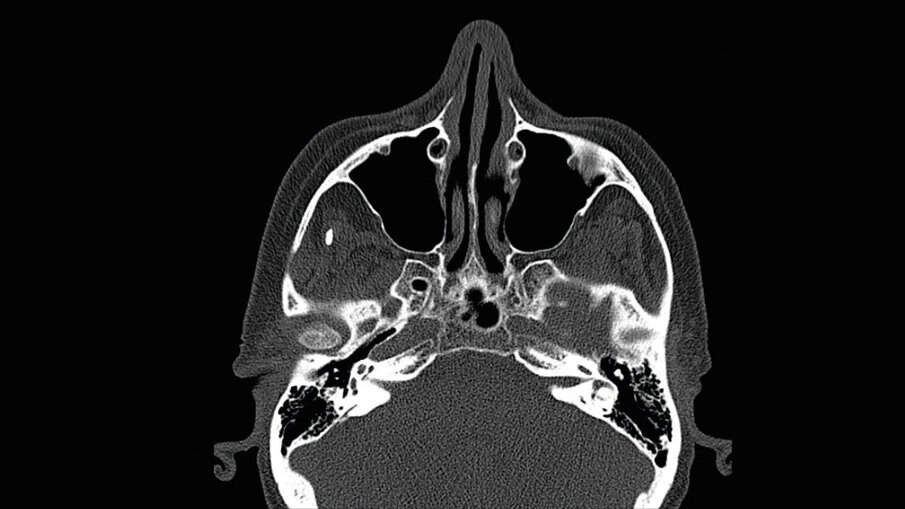

- pianificazione chirurgica della riabilitazione con valutazioni anatomiche, TC Cone-Beam, stereolitografia (SLA), funzionale al progetto protesico;

È presentata una riabilitazione con 4 impianti zigomatici (QUAD) in paziente con grave atrofia del mascellare. In questo caso la protesi con carico funzionale è stata consegnata alla paziente dopo 72 ore. Nelle immagini 1-4 viene mostrata la stereolitografia e la TC della paziente, mentre nelle immagini 5-7 viene mostrata la situazione iniziale e finale della paziente.